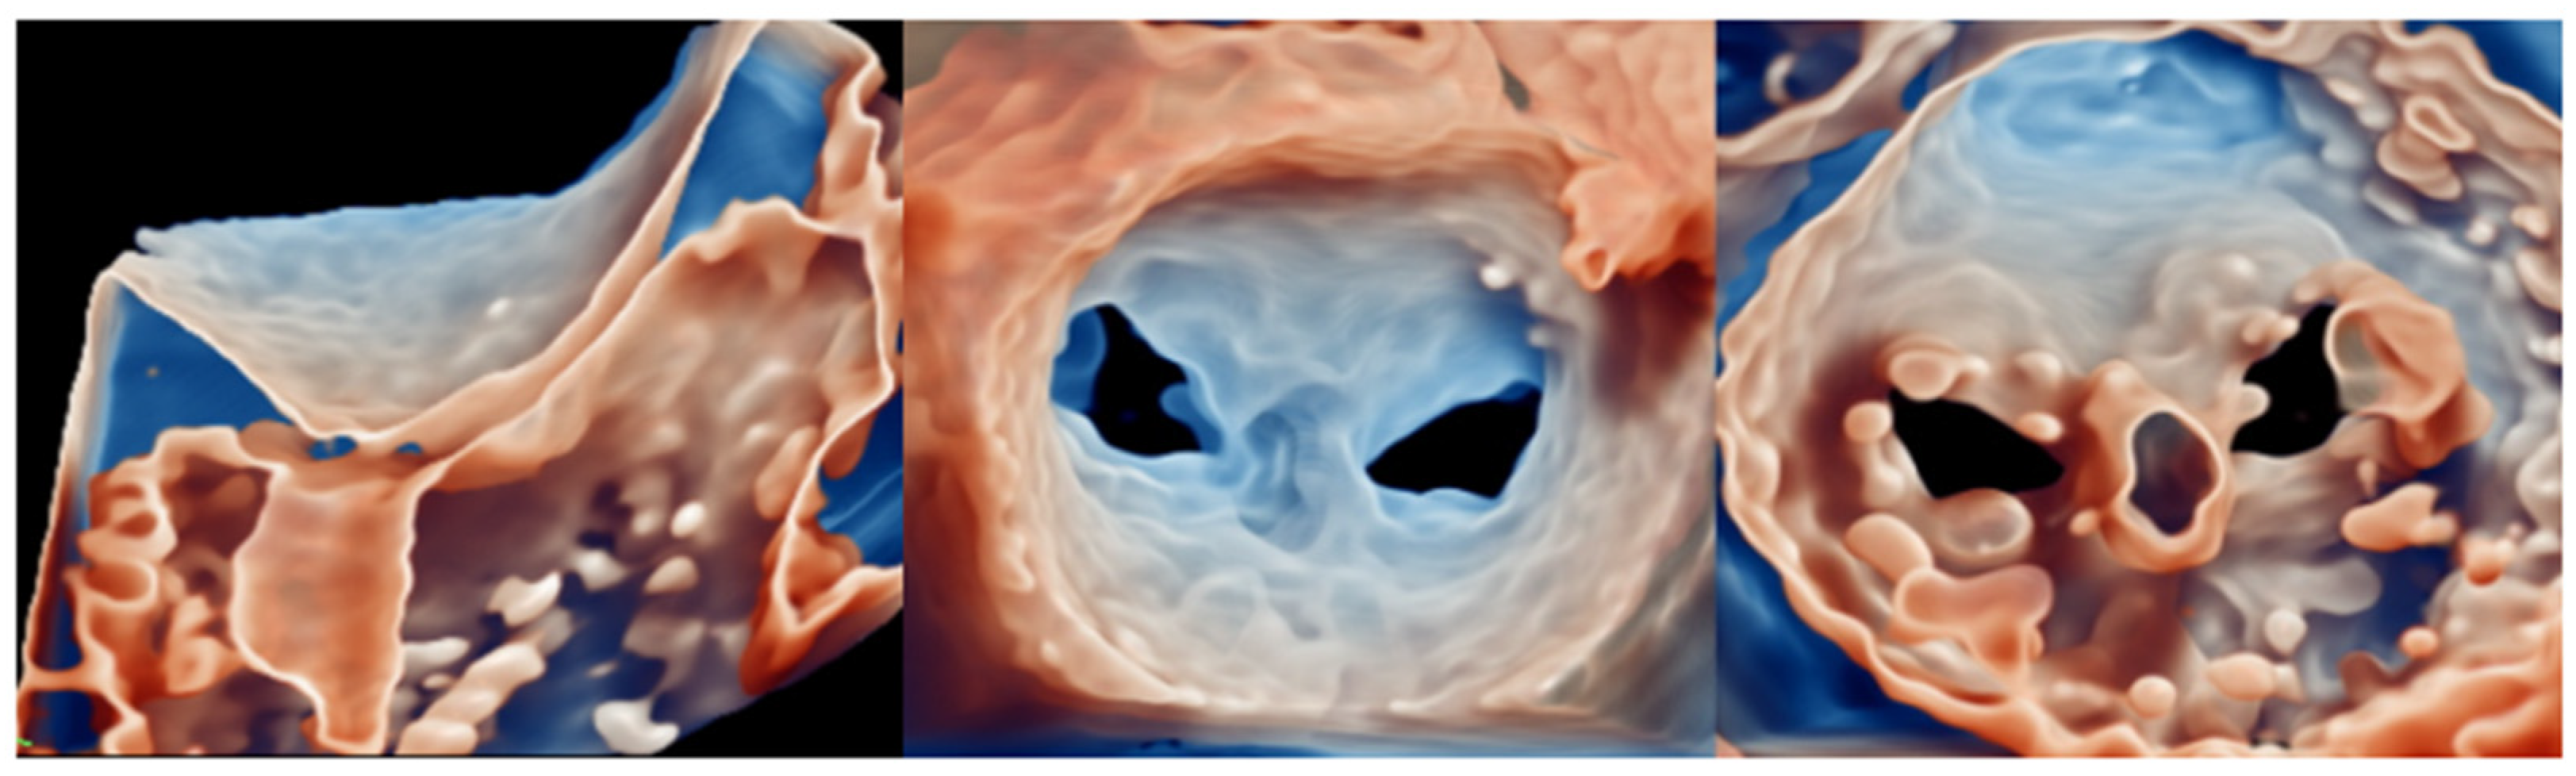

4.e TMVR

5.e TMVR

6.d TMVR